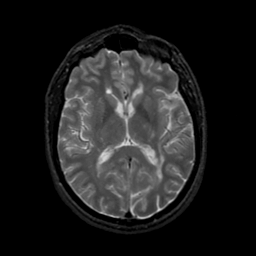

MR Study #22, December 1, 1991 -- Slice #27